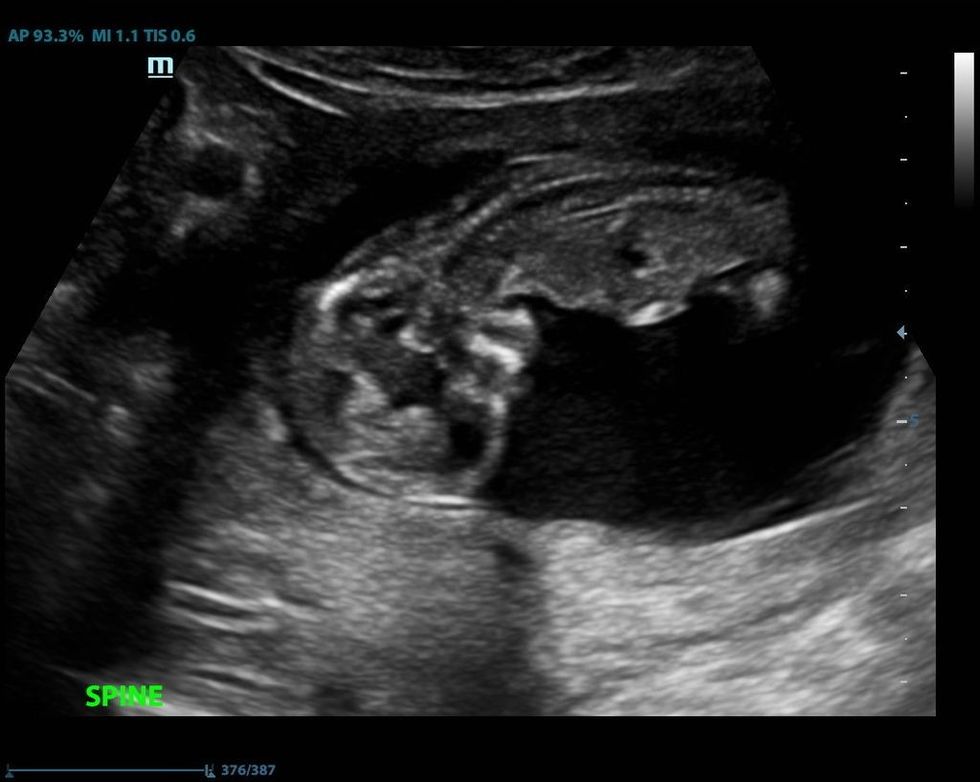

Rekomandohet që shtatzëna të mos hajë e pijë asgjë që nga darka një ditë përpara se të bëhet versioni i jashtëm cefalik. Nëse shtatzëna është Rh negative, atëherë duhet t’i jepet imunoglobulina. Përpara procedurës bëhet ekzaminimi me ultrazë për të përcaktuar saktësisht vendosjen e bebes, sasinë e lëngut amnial dhe pozicionin e placentës. Gjatë gjithë kohës përcillen rrahjet e zemrës së frytit për të parë mos ka shenja vuajtjeje. Pasi që të kryhet procedura prapë përsëritet ekzaminimi ultrasonografik.